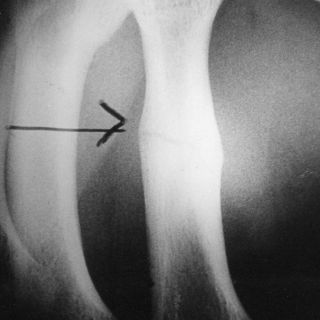

El especialista manifestó que la osteoporosis, "como su nombre lo indica, se caracteriza por la porosidad ósea que torna los huesos frágiles y por lo mismo más susceptibles a quebrarse".

Añadió que la evidencia más clara de su presencia es una fractura, siendo las de cadera las más frecuentes, aunque también se puede producir en la columna, con una tasa de mortalidad a dos años de 50 y 23 por ciento, respectivamente.

Destacó que una mujer que se fractura la cadera "tiene 50 por ciento de mortalidad a los dos años, es decir la mitad de las pacientes con fractura de cadera mueren en dos años, es una mortalidad mayor que la de cáncer de mama".

"Esto es algo sumamente importante, pero además, de esa mitad de pacientes que no fallecieron, 80 por ciento no vuelve a caminar, de ahí la importancia de la prevención", afirmó.